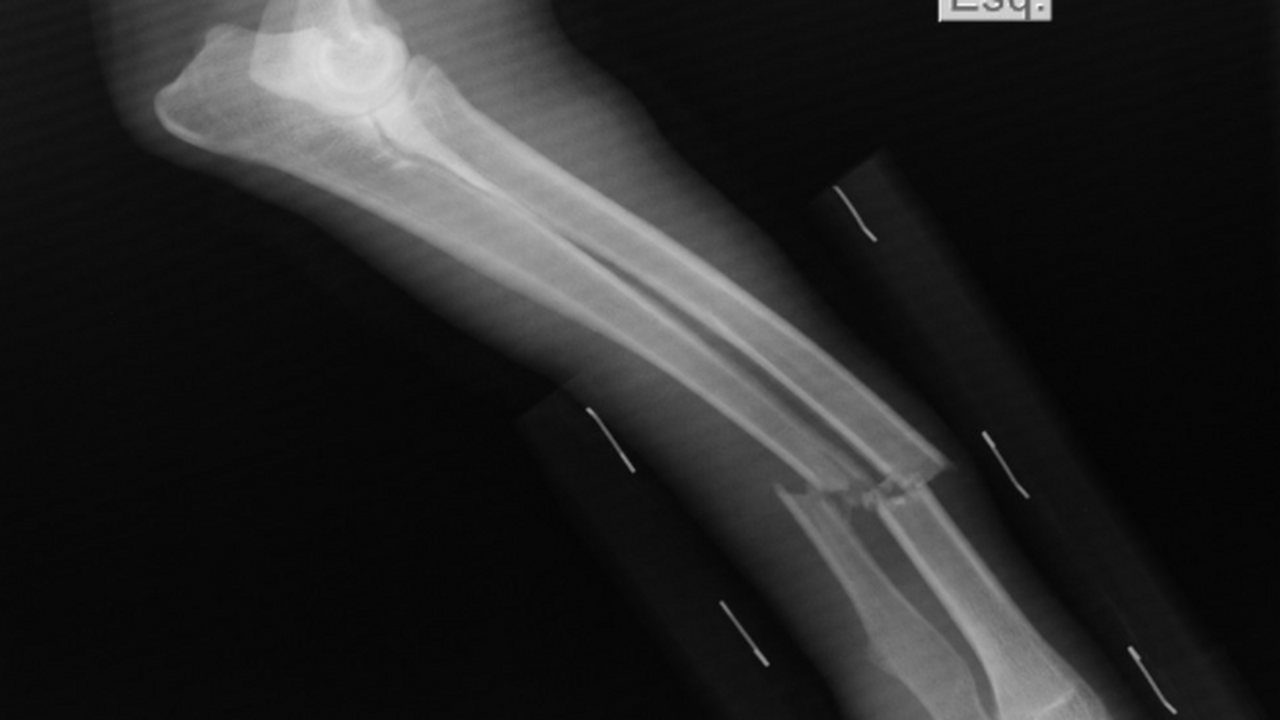

Японские ученые разработали метод лечения переломов

Исследователи из Осакского столичного университета представили революционный метод лечения переломов позвоночника с использованием стволовых клеток, выделенных из жировой ткани человека. Результаты опубликованы в журнале Bone & Joint Research.